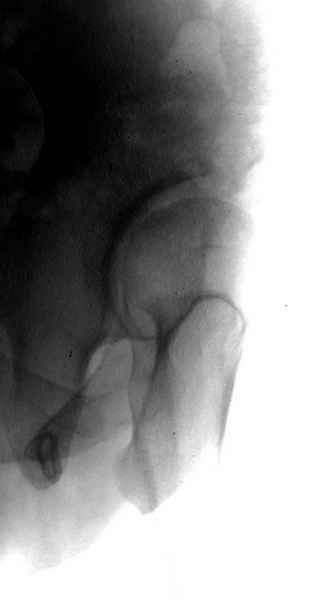

Картина типичной эволюции дисплазии сустава "кистовидная перестройка", на фоне неправильного взаймоотношения сустава "да тут угол Виберга 0 градусов" на вершине наибольшей нагрузки в вертлужной впадине образовался участок разрежения, "киста", в последующем через этот участок образуется перелом - стадия фрагментация дисплазии.

Для установки диагноза достаточно информации, на рентгенограмме передний и задний край ацетабулум образовали перекрест, "цифру восемь", указывающий на небольшую ретроверсию, а суставная щель одинаковой ширины на всем протяжении, что доказывает, что с покрытием хряща проблем нет. Головка бедра покрыта всего наполовину, это явное нарушения взаимоотношений.